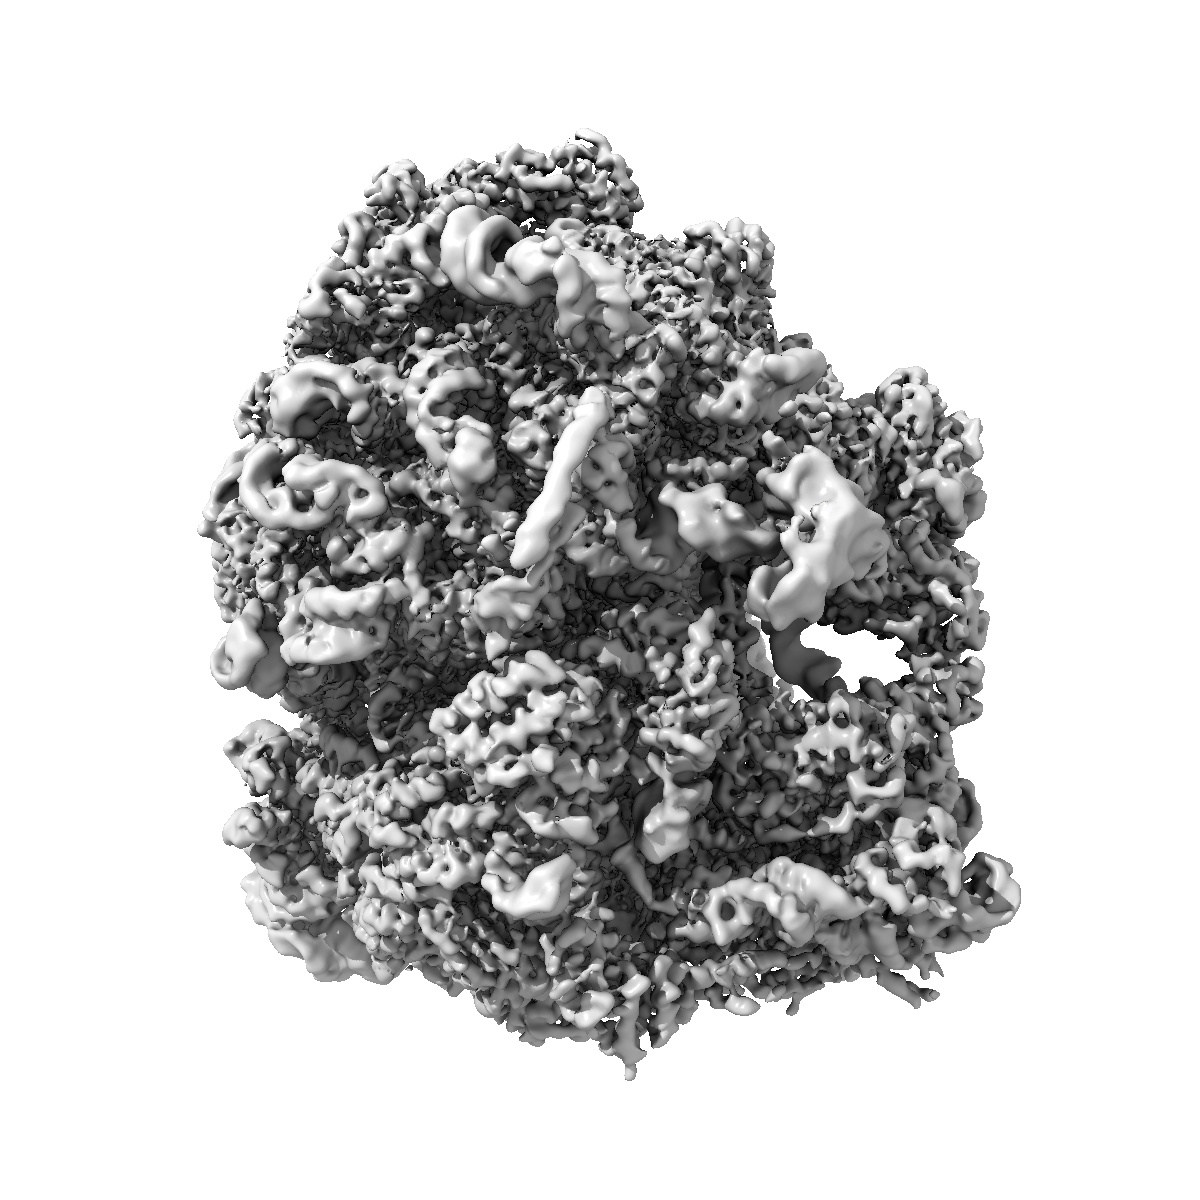

Pre-release fusidic acid-locked Escherichia coli 70S ribosome with Staphylococus aureus EF-G and FusB (FusB-EF-G-70S)

Single-particle

2.79 Å

Structural mechanism of FusB-mediated rescue from fusidic acid inhibition of protein synthesis.

Gonzalez-Lopez A , Ge X , Larsson DSD , Sihlbom Wallem C, Sanyal S , Selmer M

(2025) Nat Commun , 16 , 3693 - 3693